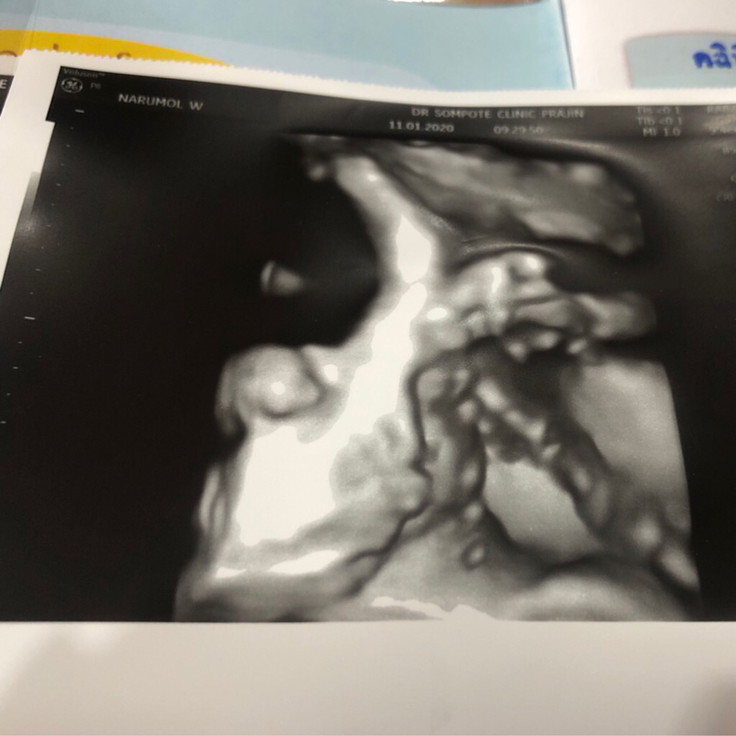

ขอดูรูปซาวของแม่ๆหน่อยค้าว่าได้ผู้หญิงผู้ชาย บ้านนี้ผู้ชายจ้าา

ผู้หญิงค่ะ

ชัดมากก